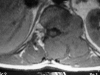

The mean survival of patients with skeletal solitary plasmocytoma is 75% at 5-year follow-up. This highly osteolytic tumor may compromise spinal stability. Radiotherapy is effective in local control of the disease, however, it is not effective in restoring spinal stability. Fracture risk and progressive vertebral collapse persist. For this reason, we must consider the need to establish the probability of progressive vertebral collapse, based on the degree of involvement of the vertebral body at the time of diagnosis. We used parameters described by Taneishi and Kaneda, as well as those of Heller and Boden to predict progressive vertebral collapse. Three cases are presented and their treatment is described.